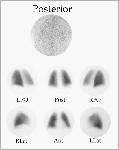

GAMMAGRAFIA DE VENTILACION-PERFUSIONLa escintigrafía o gammagrafía pulmonar continúa siendo un procedimiento útil de visualización del pulmón y el siguiente paso después de la radiografía de tórax. Los resultados del test pueden clasificarse como normales, altamente probables y sin diagnósticoUna gammagrafía de perfusión normal se caracteriza por la distribución uniforme del radiotrazador en ambos pulmones. Un resultado como el de la imagen es un buen indicador de una buena prognosis y los enfermos dentro de esta categoría no necesitan anticoagulantes. En casos como este, el diagnóstico es claro. La gammagrafía de ventilación-perfusión de alta probabilidad está caracterizada por múltiples o grandes defectos segmentales con ventilación normal y al menos un área de perfusión anormal. Esto se conoce como fallo emparejamiento de ventilación/perfusión. El primer estudio muestra una gammagrafía de alta probabilidad con múltiples defectos segmentales y ventilación normal en aquellas áreas, mientras que el segundo estudio muestra mayores defectos de perfusión lobular. Esta categoría es bastante fiable y varios autores han demostrado que el 85-87% de los enfermos de este tipo confirman la embolia pulmonar por angiografía pulmonar Sin embargo, es importante reconocer

que sólo una minoría de los enfermos con embolia pulmonar

muestra unas gammagrafías de alta probabilidad y que estos caracteres

no son patognómicos de una embolia aguda especialmente si hay

historia de émbolos

anteriores. Este ejemplo muestra los típicos hallazgos de

una gammagrafía de alta probabilidad con múltiples

defectos segmentales. Sin embargo, el episodio embólico tuvo

lugar varios meses antes del estudio. Una minoría de émbolos

no se resuelven y la perfusión pueden no haber regresado a la

normalidad. Cuando una gammagrafía de ventilación/perfusión no se ajusta a la categoría de normal o de alta probabilidad, se considera que el estudio no arroja un diagnóstico y por tanto, se requieren otras investigaciones. La mayoría de los casos caen dentro de esta categoría que se caracteriza por gammagrafías con defectos subsegmentales o defectos de cualquier tipo que no se emparejan con anomalías observadas en las radiografías o en los gammagrafías de perfusión. Por ejemplo, este estudio fué interpretado como mostrando un pequeño defecto subsegmental. Pero sin la flecha, el estudio fué subseguientemente definido como normal por un buen número de especialistas. En conclusión, las gammagrafías de pulmón son pruebas sensibles que establecen el diagnóstico de una embolia pulmonar cuando son normales. Los enfermos con gammagrafías de alta probabilidad pueden ser tratados a menudo sin más estudios. Aquellos que en los que el diagnóstico no se seguro necesitan posteriores investigaciones. |